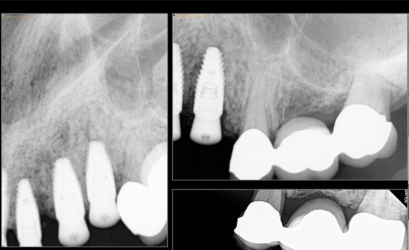

Treatment planning pt for implant bridge.

Im not sure if i should graft the 5 site and wait or place implant in 4 site and do mesial cantilever.